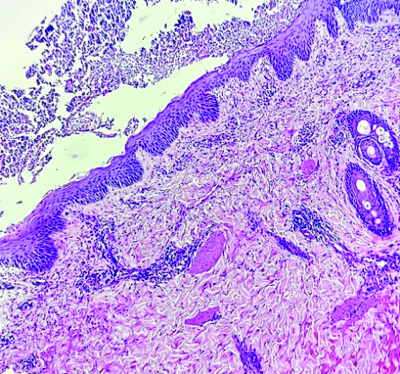

Histopathological examination {Haematoxylin and Eosin (H&E)} of a 4 mm punch biopsy specimen taken from a lesion on her arm revealed a large sub-corneal pustule filled with neutrophils and neutrophilic debris, along with mild acanthosis and spongiosis in the epidermis. The superficial dermis showed a neutrophilic infiltrate extending into the epidermis, along with a deep dermal perivascular and periadnexal neutrophilic infiltrate [Table/Fig-3]. Laboratory investigations indicated a raised Total Leucocyte Count (TLC) of 12.2×109/L (neutrophils, 89%), elevated erythrocyte sedimentation rate (64 mm/hr) and C-reactive protein (35.55 mg/L), hypocalcaemia (7.2 mg/dL), hypomagnesaemia (1.3 mg/dL), hypoalbuminaemia (2.7 g/dL) and normal parathormone levels. Anti-phospholipid antibody and antinuclear antibody tests were negative.

Histopathological examination showing mild acanthosis and spongiosis. A large sub-corneal pustule is seen filled with neutrophils and neutrophilic debris. Superficial dermis shows neutrophilic infiltrate extending into the epidermis while deep dermis shows perivascular and periadnexal neutrophilic infiltrate (H&E, 40X).